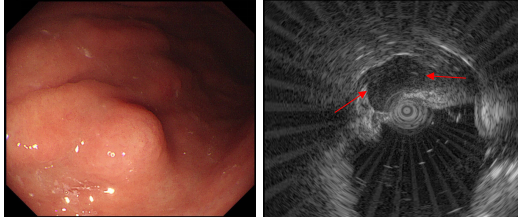

胃体中部黏膜下隆起,超声内镜提示起源于固有肌层

67岁刘阿姨,因腹部不适在胃镜检查时,发现胃体中部有一处直径约1.0cm的粘膜下隆起,经超声内镜(EUS)检查后,初步诊断为起源于固有肌层的“胃间质瘤”(GIST)。